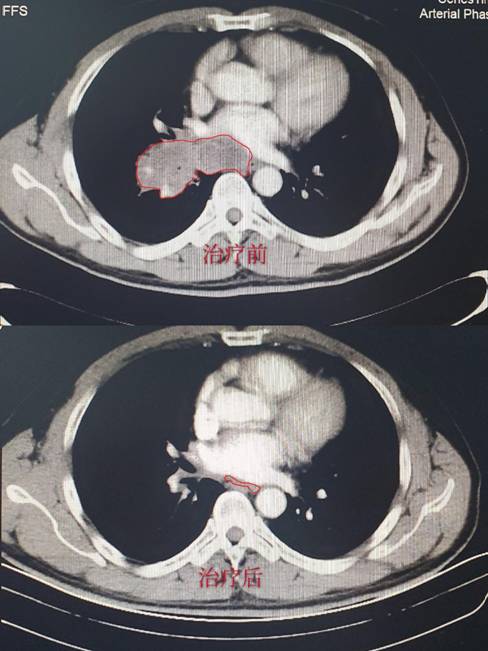

病例2:应某某,诊断为:左肺小细胞癌广泛期。治疗之前存在严重咯血及咳嗽,治疗3天后就停止咯血,咳嗽明显好转,经 2周期治疗后免费复查胸部CT,肿瘤缩小80%。(CT结果如下,红色线框内为肿瘤组织。)